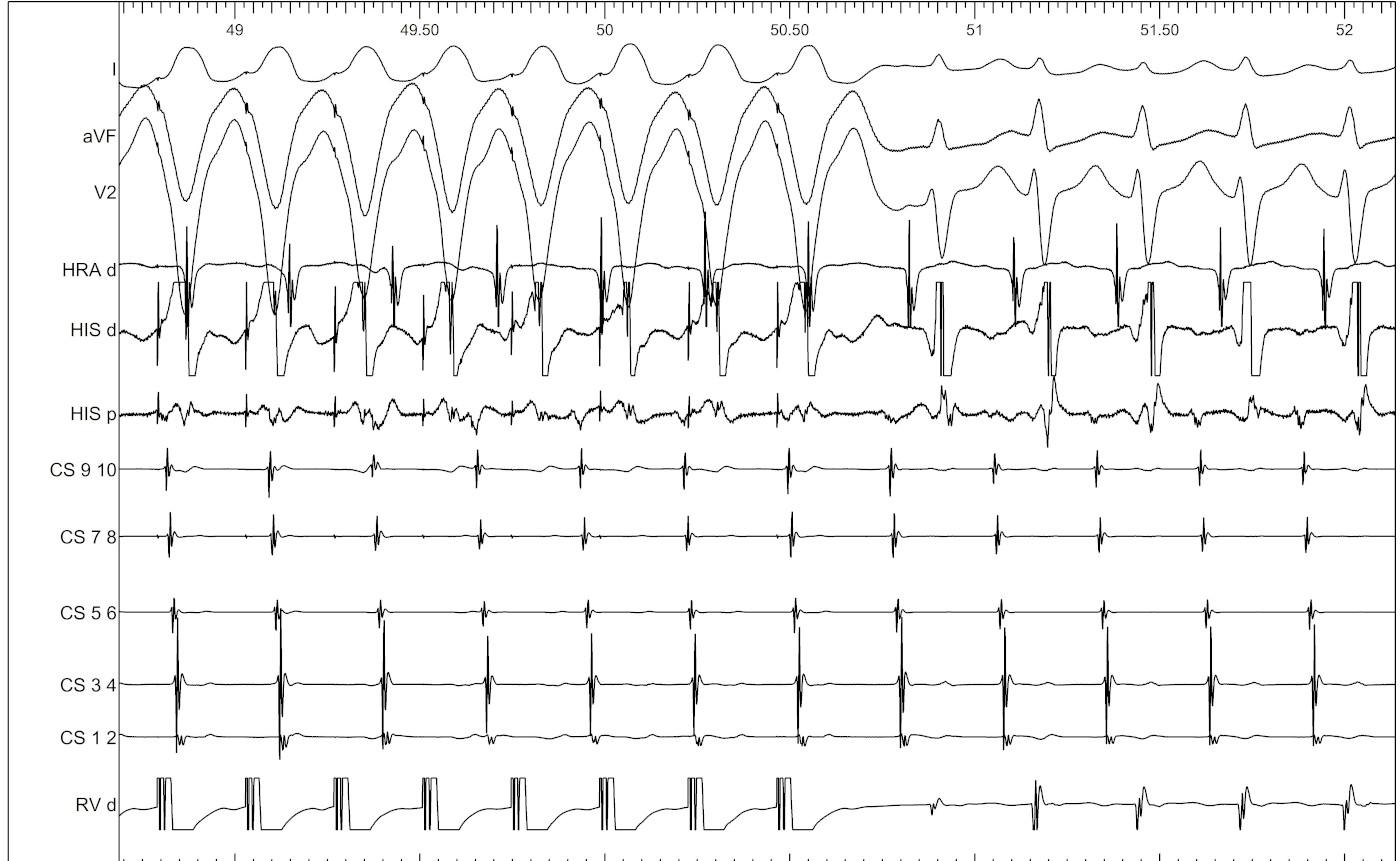

VOP - Setting up

• 20 to 30 ms shorter than tachycardia CL

• Sync on

vop_beats.png

Stepwise approach

• Was the atrium entrained ?

• Which is the last entrained A ?

• What is the return response - VAV vs VAAV

• What is the cPPI-TCL ? (VAV)

• What is the SA-VA (VAV)

Tachycardia continues

vav_avnrt.jpg